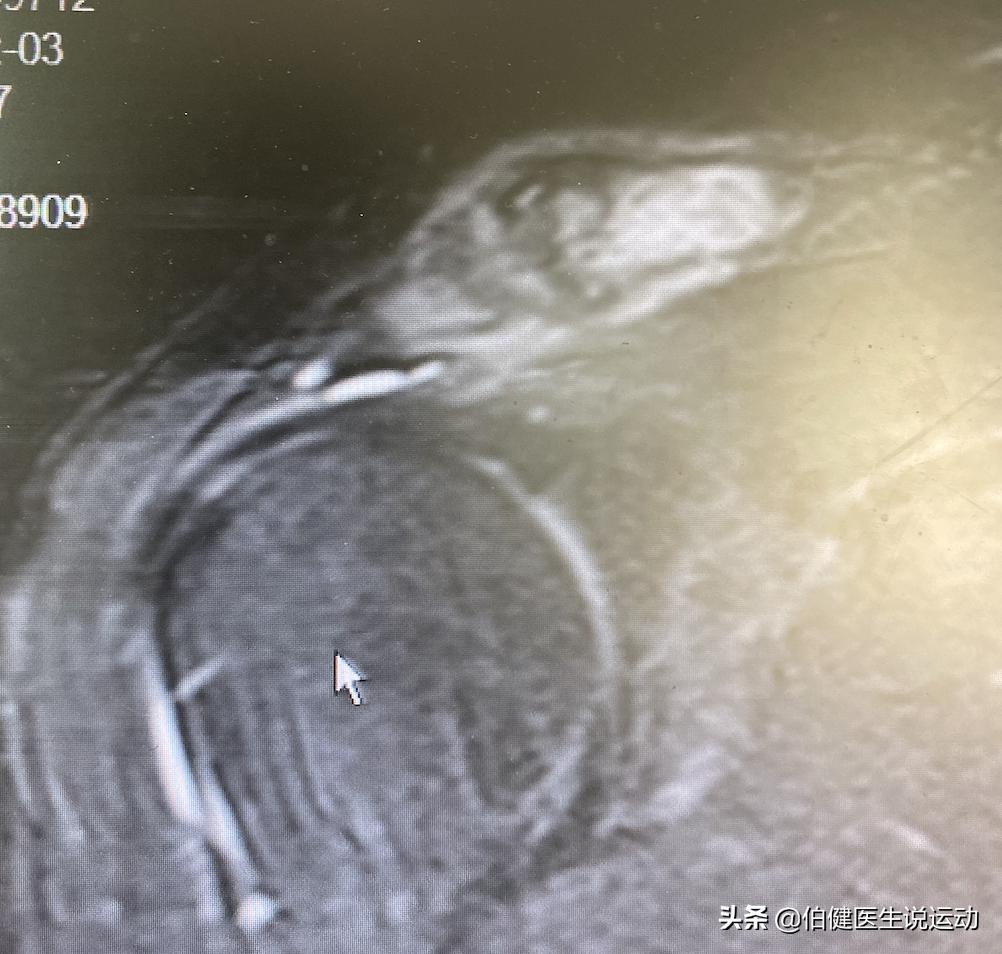

他没有给图我看。但我根据他的描述找了一个近似病人的图像,方便大家理解。

肩峰关节炎,锁骨端骨髓水肿

MR显示伴有软骨下骨囊变的肩锁关节退行性变。锁骨远端和肩峰都可以发现有骨水肿